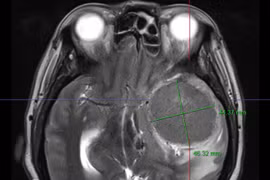

Đau đầu, bất ngờ phát hiện u màng não khổng lồ ăn sâu vào não

Chưa hề phát hiện bệnh lý về sọ não, đau đầu nhiều uống thuốc không đỡ, bệnh nhân bất ngờ phát hiện u não 50mmx 70mm. Phải 8 tiếng các bác sĩ mới lấy được khối u phát triển sâu vào tổ chức não.